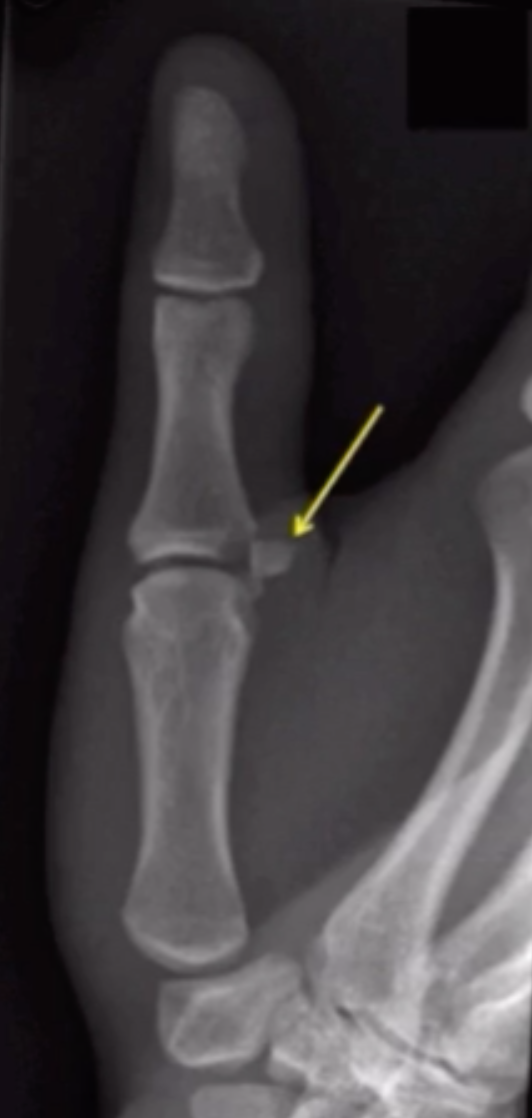

Gamekeeper thumb

• Ulnar collateral ligament of thumb avulsion fracture

• 1/3 have avsulsion fracture

• 2/3 have just ligament injury

• Case courtesy of Leonardo Lustosa, Radiopaedia.org, rID: 98585